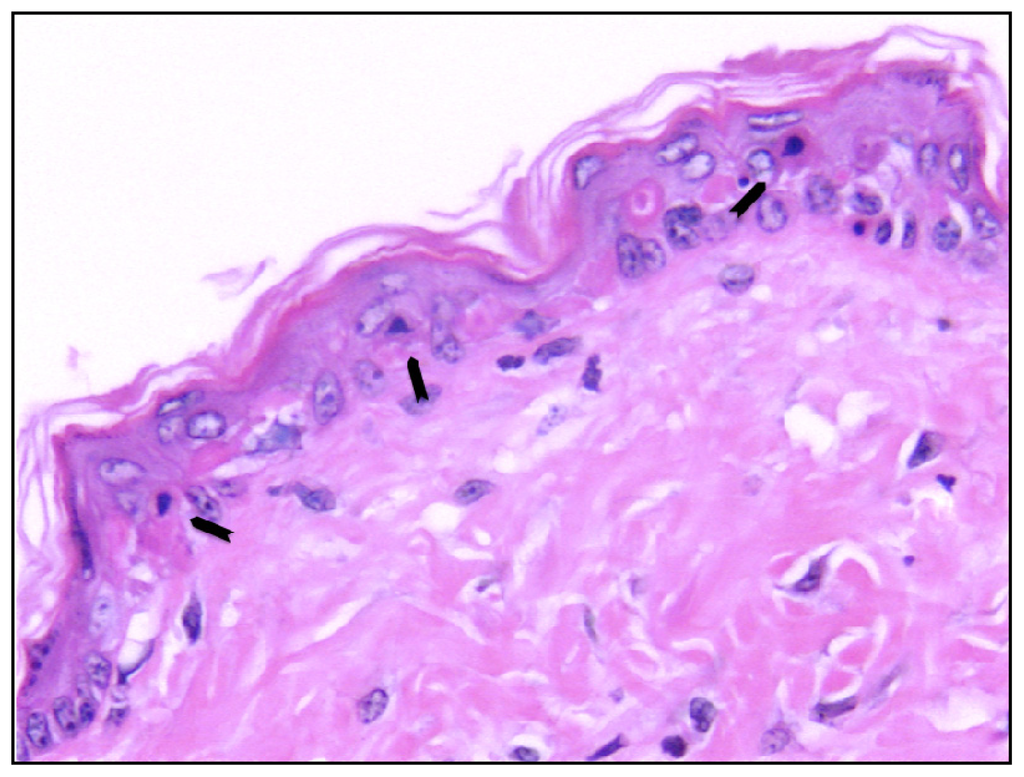

- Sheehan, J.M.; Young, J.R. The sunburn cell revisited: An update on mechanistic aspects. Photochem. Photobiol. Sci 2002, 1, 365–377. [Google Scholar]

- Claerhout, S.; van Laethem, A.; Agostinis, P.; Garmyn, M. Pathways involved in sunburn cell formation: Deregulation in skin cancer. Photochem. Photobiol. Sci 2006, 5, 199–207. [Google Scholar]